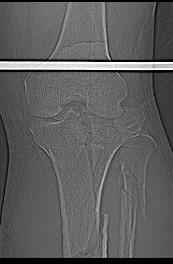

Интрамедуллярный остеосинтез диафизарного перелома тут возможен, но в первую очередь надо с помощью КТ уточнить повреждение суставного конца. Импрессионный перелом наружного мыщелка явный есть, может, и медиальная колонна повреждена, так что надо в первую очередь планировать открытую репозицию с замещением дефекта с фиксацией пластиной или аппаратом. Если получается технически, можно поверх уже синтезированного стержнем диафиза.

Уважаемый Александр Николаевич! Прошу прощения за некачественные сканы. КТ вообще-то реально, но сложности с транспортировкой больного в соседний корпус (такая перевозка и перекладывание для больных - дополнительная травма). По Р-граммам медиальный отдел вроде целый, но наружный мыщелок "отклячен" и суставная поверхность явно просела. У нас весь вопрос в методе фиксации или же их сочетании - одна пластина, опорная пластина и стержень (я так понял, что вы предлагаете сначала фиксировать диафиз, а потом заняться мыщелком?), винты и стержень, аппарат...Опять же состояние м/тканей (плотный отек, кровоизлияние)...

Пациенту сделали КТ - ухитрились сделать на шине Белера (не давал положить прямую ногу) - срезали передний отдел. Планируется на пятницу (24.12) на операцию - синтез длинной мыщелковой LCP-пластиной Synthes :). Отек ближе к слову умеренный (окружность голени +4 см по сравнению со здоровой). КТ и снимок на вытяжении прилагаются.